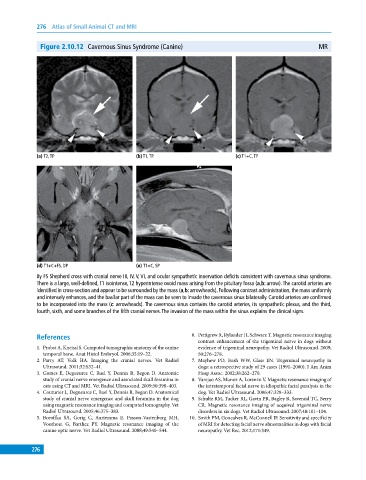

Figure 2.10.12 Cavernous Sinus Syndrome (Canine) MR

(a) T2, TP (b) T1, TP (c) T1+C, TP

(d) T1+C+FS, DP (e) T1+C, SP

8y FS Shepherd cross with cranial nerve III, IV, V, VI, and ocular sympathetic innervation deficits consistent with cavernous sinus syndrome.

There is a large, well‐defined, T1 isointense, T2 hyperintense ovoid mass arising from the pituitary fossa (a,b: arrow). The carotid arteries are

identified in cross‐section and appear to be surrounded by the mass (a,b: arrowheads). Following contrast administration, the mass uniformly

and intensely enhances, and the basilar part of the mass can be seen to invade the cavernous sinus bilaterally. Carotid arteries are confirmed

to be incorporated into the mass (c: arrowheads). The cavernous sinus contains the carotid arteries, its sympathetic plexus, and the third,

fourth, sixth, and some branches of the fifth cranial nerves. The invasion of the mass within the sinus explains the clinical signs.